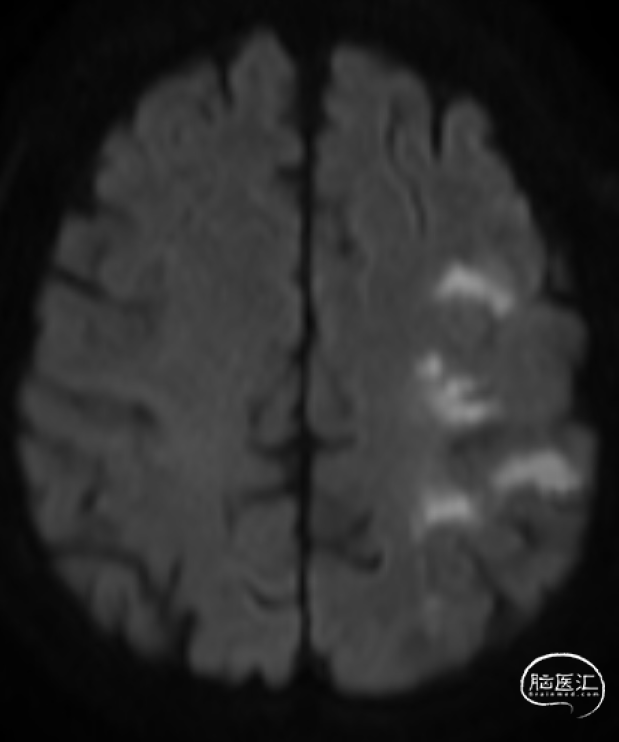

➤2024.2.28 头颅MRI+MRA

左额顶叶/左枕叶亚急性期脑梗死,左侧大脑中动脉M1段重度狭窄。